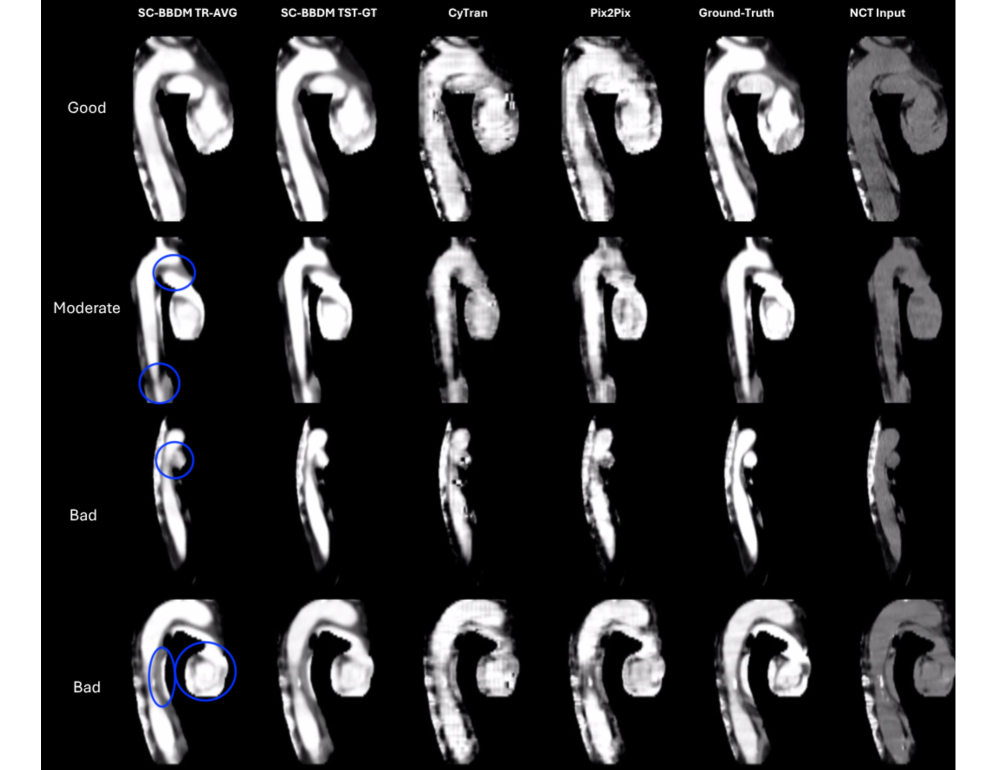

Qualitative results: To gain deeper insight, generated images were reviewed by a radiologist alongside the ground truth. To ensure consistency, we applied appropriate windowing to the ground-truth CTA, input NCT, and generated CTA with a window width of 350 HU and a window level of 50 HU. This adjustment highlights the relevant anatomic structures, allowing for a more accurate assessment of contrast enhancement, particularly in the aorta and heart regions. We have provided videos showing slice-wise performance of SC-BBDM compared to the ground-truth, along with the baselines (CyTran and Pix2Pix), and the input NCT volumes in the Supplementary Material of this paper.

Figure 3 is divided into AV slices (left) and CAV views (right) and groups SC-BBDM’s predictions into three bands: Good, i.e. virtually indistinguishable from the contrast ground truth; moderate, i.e. minor shape or intensity deviations that still leave anatomy recognizable; and bad, i.e. pronounced artifacts that obscure or distort vascular structure. In AV moderate case shows exaggerated fat planes between the main pulmonary trunk and aortic arch (top) and artifactual narrowing of the descending aorta (bottom). Bad cases exhibit blurring of the anatomical borders (as outlined) due to a combination of artifact and hyperenhancement. In CAV, moderate case demonstrates blurring of anatomical borders and loss of cardiac chambers due to hyperenhancement, and bad cases exhibit artifactual narrowing of the aorta and its branches, as well as blurring of cardiac chamber walls. Despite these view‑specific shortcomings, SC-BBDM outputs preserve vessel geometry and intensity distributions more faithfully than CyTran and Pix2Pix, whose images are marred by grid‑pattern texture and streak artefacts.

Refer to caption

Figure 3: Comparison of synthesized images using different methods: the AV dataset on the left side, and the CAV dataset on the right side. Columns represent different approaches. TR-AVG means using the average style key of training, and TST-GT means using the ground-truth style key of test samples. Blue circles highlight notable artifacts or discrepancies.